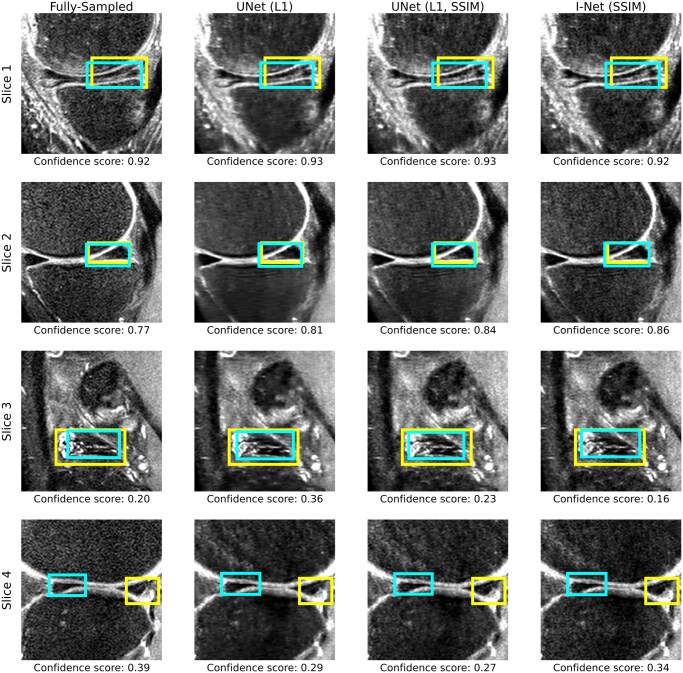

Materials and methods: This retrospective study included 947 knee MRI examinations; 51 were excluded for poor image quality, leaving 896 participants (mean age, 44.7 ± 15.3 years; 472 women). Using 8-fold undersampled data, DL-based reconstructed images were generated. An object detection model was trained on original, fully sampled images and evaluated on 1 original and 14 DL-reconstructed test sets to identify meniscal lesions. Standard reconstruction metrics (normalized root mean square error, peak signal-to-noise ratio, and structural similarity index) and anomaly detection metrics (mean average precision, F1 score) were quantified and compared. Two radiologists independently reviewed a stratified sample of 50 examinations unassisted and assisted with AI-predicted anomaly boxes. McNemar's test evaluated differences in diagnostic performance; Cohen's kappa assessed interrater agreement.

Results: On the original images, the anomaly detection model achieved the following: 70.53% precision, 72.17% recall, 63.09% mAP, and a 71.34% F1 score. Comparing performance among the undersampled reconstruction datasets, box-based reconstruction metrics showed better correlation with detection performance than traditional image-based metrics (mAP to box-based SSIM, r = 0.81, P < .01; mAP to image-based SSIM, r = 0.64, P = .01). In 50 participants, AI assistance improved radiologists' accuracy on reconstructed images. Sensitivity increased from 77.27% (95% CI, 65.83-85.72; 51/66) to 80.30% (95% CI, 69.16-88.11; 53/66), and specificity improved from 88.46% (95% CI, 83.73-91.95; 207/234) to 90.60% (95% CI, 86.18-93.71; 212/234) (P < .05).